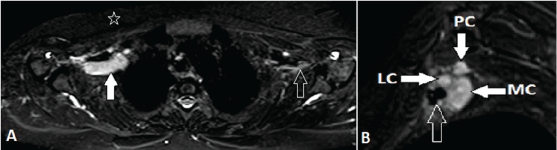

| Figure 7: A 57-year-old female, known case of postoperative and post radiotherapy carcinoma right breast with isolated intraneural metastasis. A, Axial fatsuppressed T2-weighted MR image shows isolated thickening and abnormal high signal of cords of the BP (white arrow) on right side. Note the normal left cords of plexus (open arrow). No residual or recurrent soft tissue in the post-operative bed (star). B, oblique sagittal fat-suppressed T2-weighted MR image better demonstrates the exact thickening and abnormal high signal of the cords of the brachial plexus (white arrows) in close proximity to the axillary vessels (open arrow). | ||